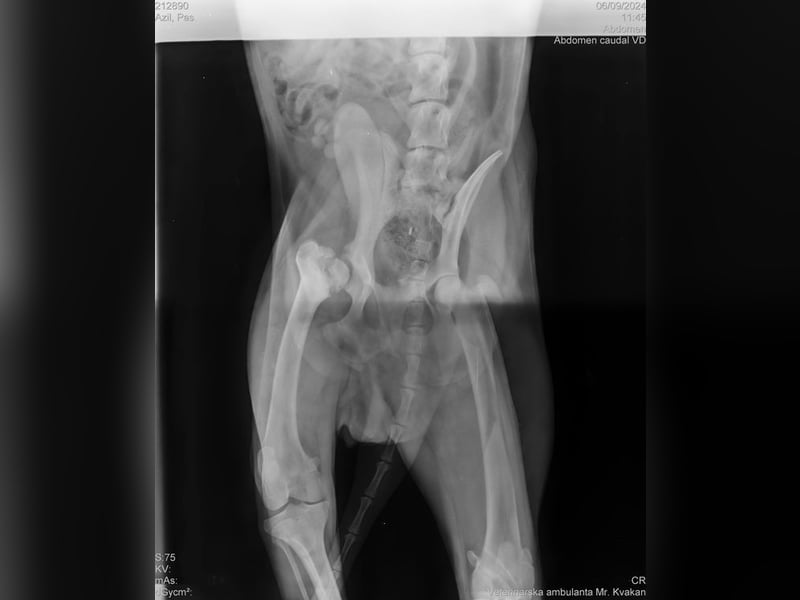

Bemerkungen: Ein Hinterbein ist etwas kürzer

Wir durften ihn deshalb ohne Probleme mit ins Tierheim nehmen, da Yondu Probleme mit der Hüfte und ein etwas kürzeres Beinchen hat. Youdu hat bei einen Besuch beim Tierarzt entsprechende Röntgenbilder von Hüfte und Hinterbeinchen, die den Interessierten in der Bildergalerie zur Verfügung gestellt werden.